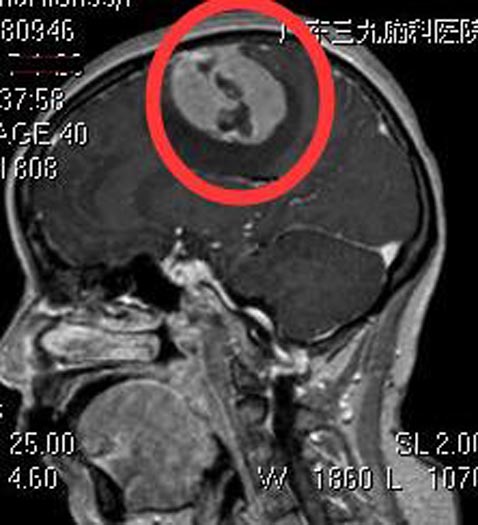

三天前,莲姨发热、头痛、头晕,再次出现左侧肢体抽搐,并左侧肢体乏力,不能行走。当地医院头颅CT检查提示:右侧额顶部占位,考虑肿瘤性病变,建议上级医院进一步治疗。广东三九脑科医院头颅MR检查提示:右侧额顶部中央浅表区镰旁占位性病变,大小约为4.5cm×5.2cm×4.2cm,考虑脑膜瘤。

综合神经外科鲁明主任主刀,在全麻下行右侧额顶部镰窦旁脑膜瘤切除术,显微镜下见右侧额顶灰白色肿瘤组织,质中,与脑膜及大脑镰粘连紧密,部分肿瘤侵犯上矢状窦,镜下将肿瘤全切除,手术经过顺利。术后没有了抽搐,莲姨回家的第一件事就是继续她的广场舞。术后病理结果提示:脑膜瘤,WHO I级。